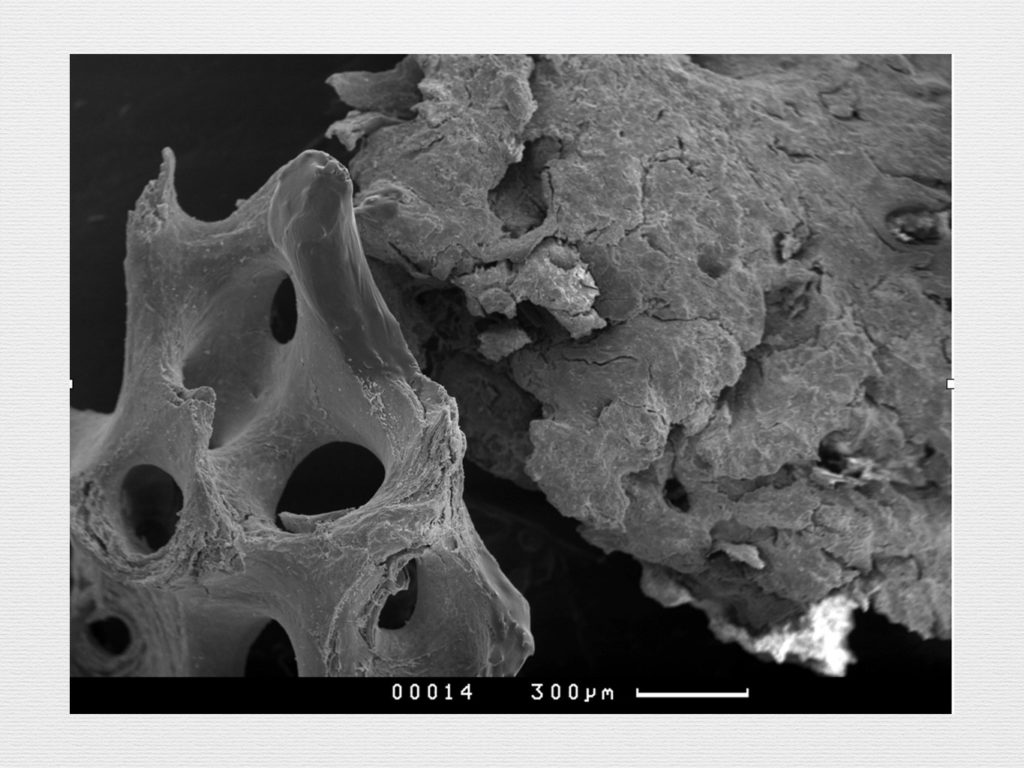

Принцип направленной костной регенерации. Костная регенерация под защитой мембраны Биоматрикс

Принцип направленной костной регенерации. Костная регенерация под защитой мембраны Биоматрикс

Принцип направленной костной регенерации. Костная регенерация под защитой мембраны Биоматрикс